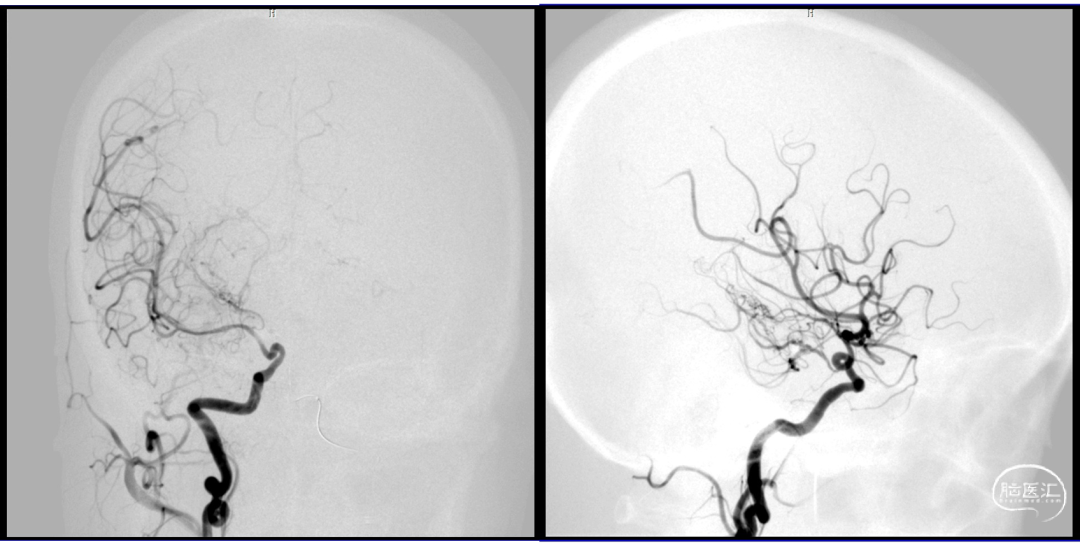

微导管超选

球囊保护下微导管造影证实假性动脉瘤

球囊保护下25%gb栓塞

2023-08-30

术后造影:假性动脉瘤消失